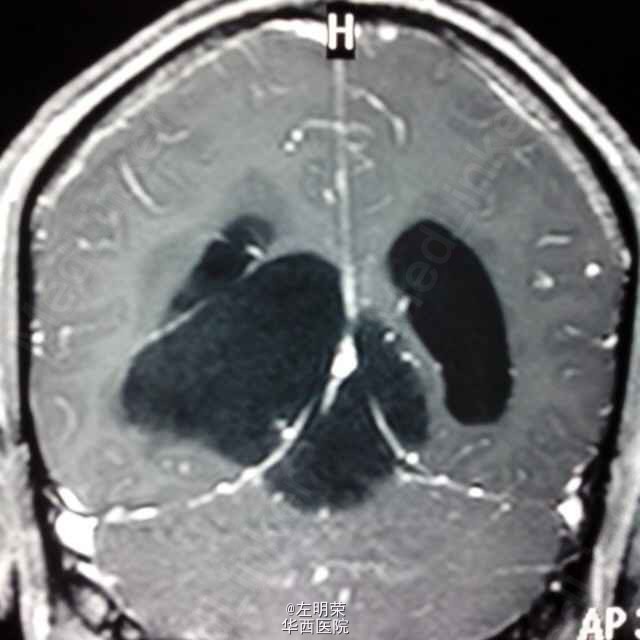

中年男性患者,“反复头痛一年”入院。查体未见明显异常;头部MRI示:松果体区占位,梗阻性脑积水。术中见病变位于右侧脑室三角区,病变范围广泛,侵及丘脑,脑干背侧,松果体区,呈白色珍珠状,质脆,切除过程中出血少,有白色坚韧包膜,予以全切,患者术后恢复良好;病理结果:松果体区表皮样囊肿。